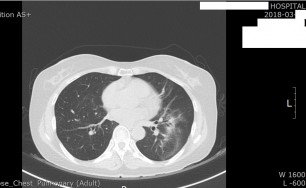

비결핵항산균에 감염된 폐사진